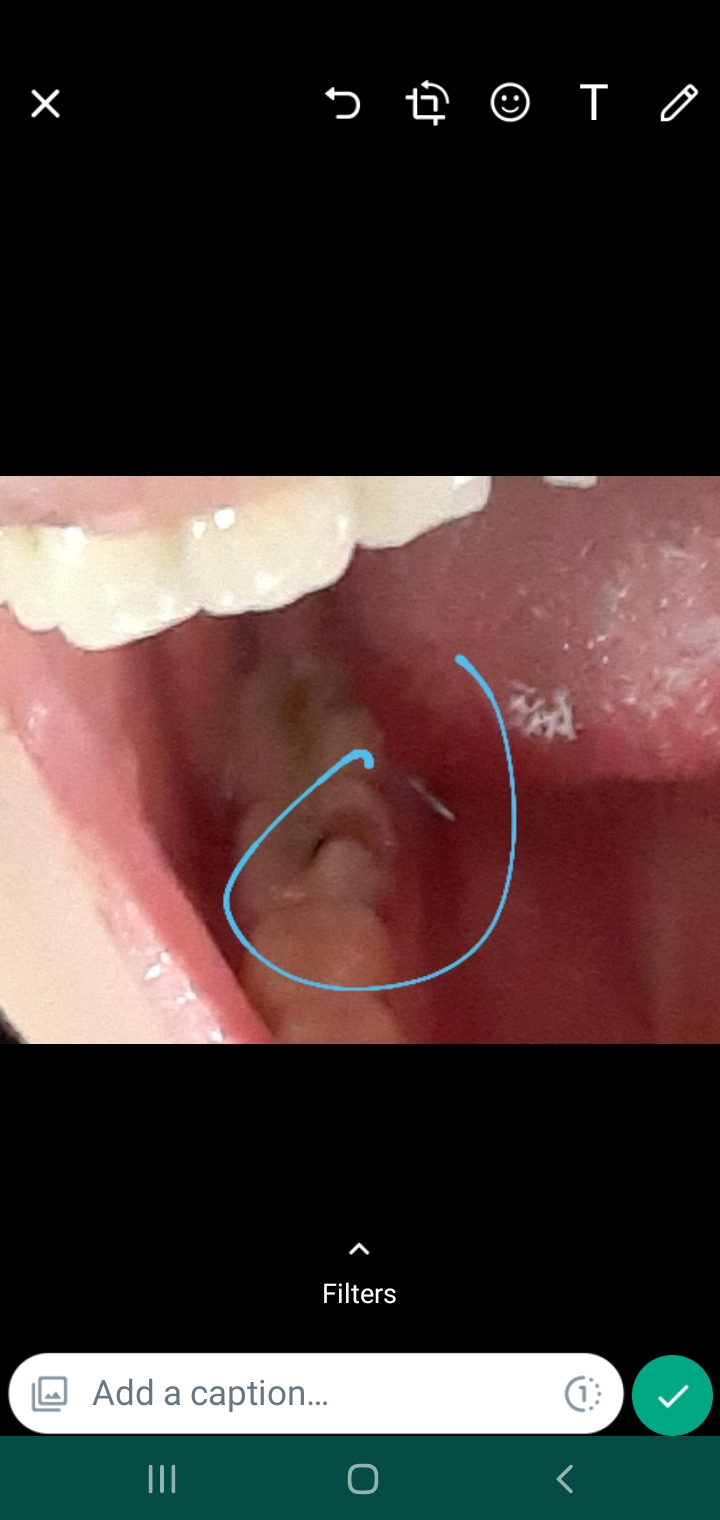

وقتی دهنمو باز میکنم این شکلی میشه این سمت

وقتی دهنمو باز میکنم اون قسمتی که عکس دادم میاد بالا

نه اخه فقط وقتی دهنمو باز میکنم معلوم میشه ولی اون طرف صورتم اینجوری نمیشه

وقتی دهنتو باز میکنی ورم میکنع؟ یا در حالت عادی ورم داره؟

اخه من وقتی باز و بسته میکنم معلوم میشه

در حالت عادی ورم داره. ولی وقتی باز میکنم بیشتر میشه!

البته برای شما شبیه عفونت هم هست